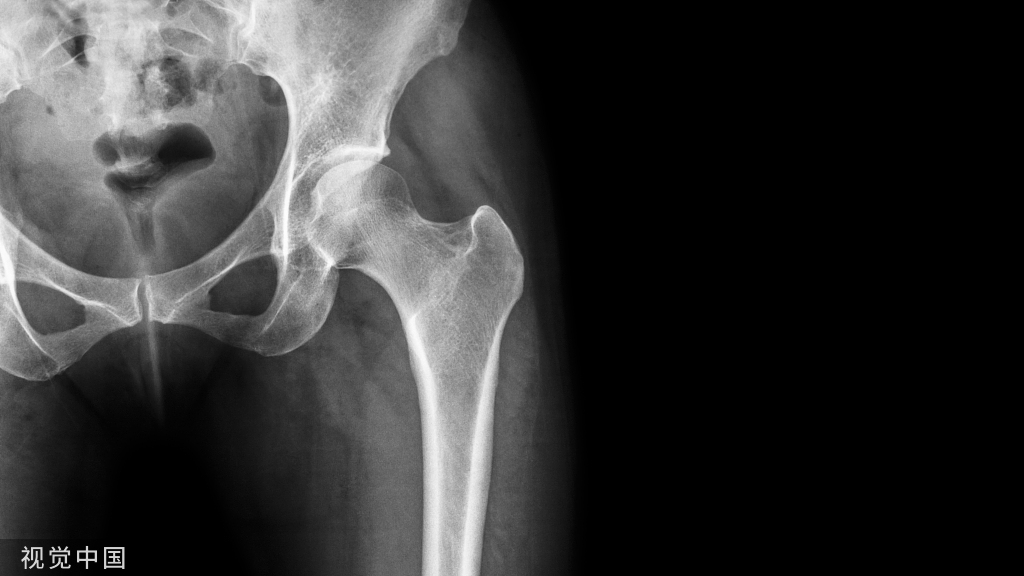

四、桡骨远端关节置换

关节置换用于严重关节内粉碎骨折的治疗已应用于肱骨近端骨折、肱骨远端骨折、胫骨平台骨折等。同理,关节置换也可用于桡骨远端骨折。适用于严重粉碎性、关节内、骨质疏松性骨折的一期治疗,或内固定失效的二期翻修。通常采用桡背侧切口,自第3/4间室间进入。